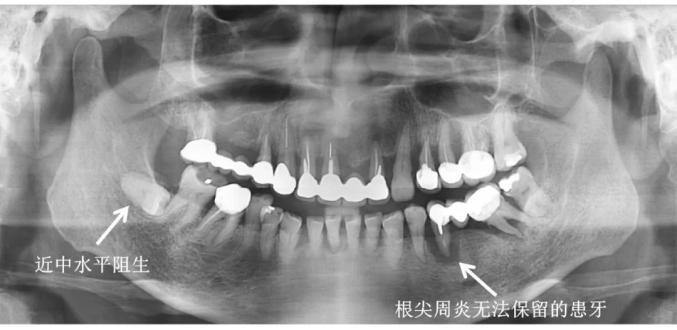

如果龋齿已经进展到牙神经发炎(不可逆牙髓炎),甚至根尖周炎,则需要做根管治疗,控制炎症,之后再做修复。

一般来说,如果智齿长的位置比较端正,也没有影响到其他牙齿,不会对口腔健康造成危害,没有疼痛不适感,那或许就可以不拔。